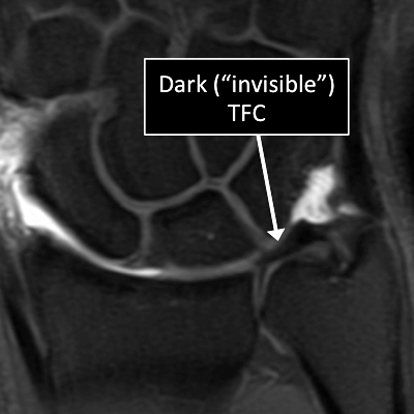

- In the wrist, as in many other parts of the body there are certain structures that can’t be seen (they look black or dark) with the standard MRI.

- There are new “software” programs that allow us to see structures with different contrast (bright versus dark).

- Some of these “invisible” or dark structures are unique to the wrist (Triangular Fibrocartilage or TFC) and others are found in other parts of the body (e.g. cartilage, tendons, ligaments, cortical bone).

Wrist MRI examinations using the standard MRI techniques (top) and translational MRI techniques (bottom).